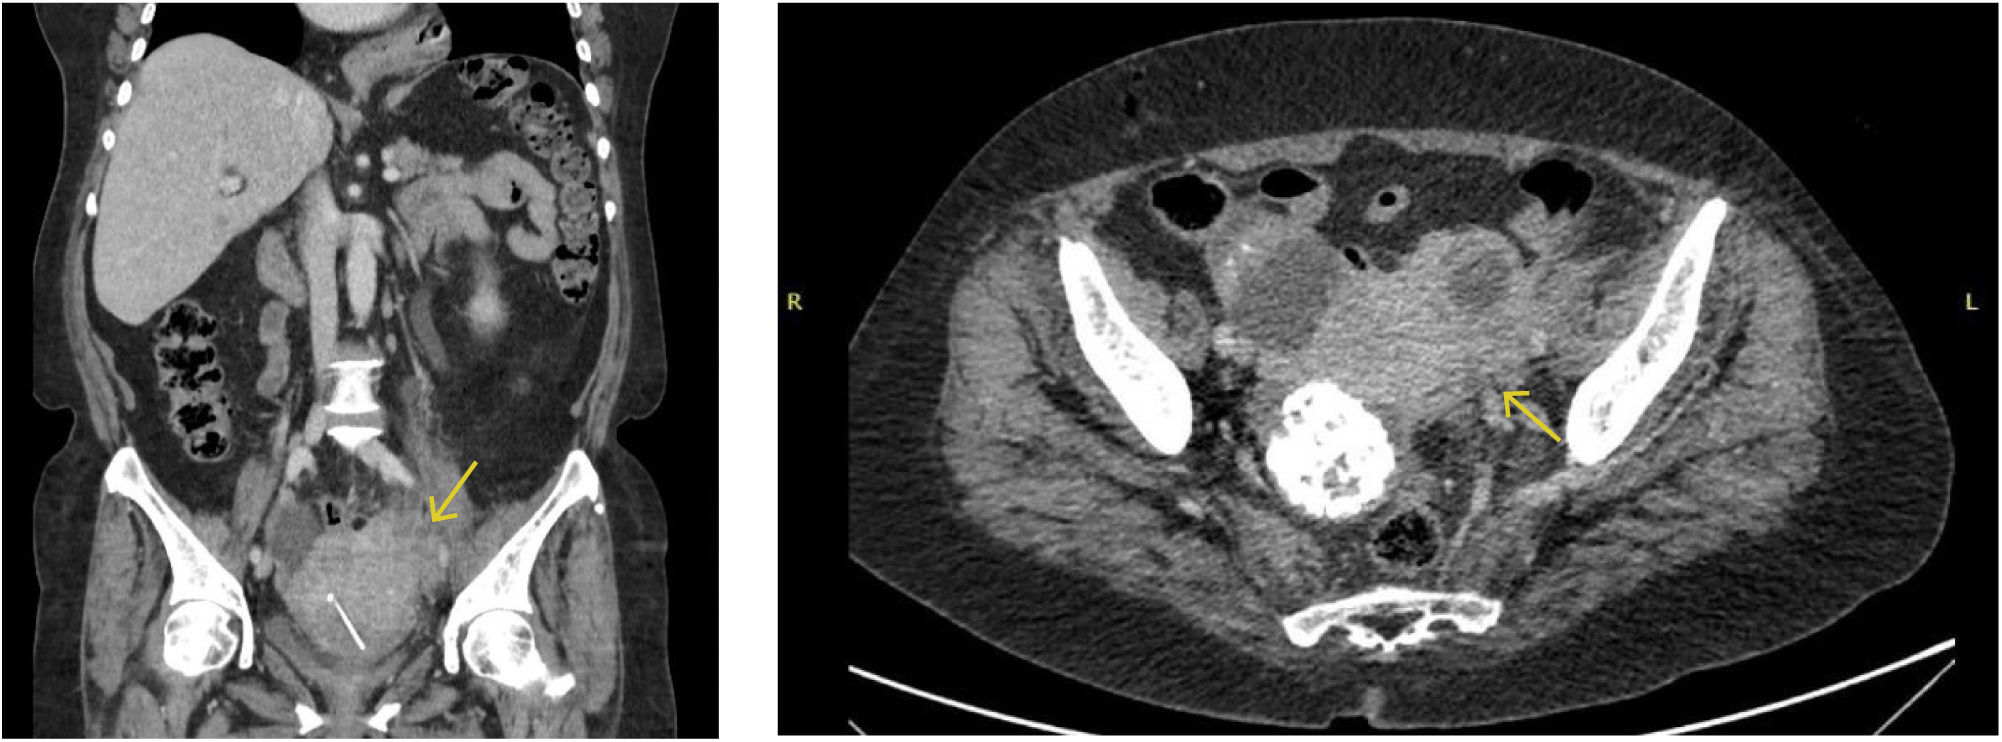

Se complementa el estudio con una tomografía de tórax abdomen y pelvis, que evidencia un gran aumento de volumen uterino con extensión anexial izquierda con áreas quísticas de abscedación, hallazgos que concluyen como compatibles con actinomicosis pélvica, con evidencia además de un DIU (Figura 1).

Tomografía computada de abdomen y pelvis. Corte coronal (a) y corte axial (b). Aumento de volumen masiforme del útero con extensión al anexo izquierdo con múltiples imágenes quísticas con paredes engrosadas, algunas sugerentes de abscedación, con aumento de densidad del tejido adiposo de aspecto inflamatorio infeccioso. Al interior de masa se observa DIU.